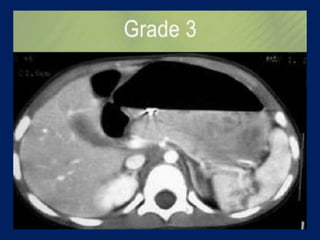

This document discusses imaging of the spleen and summarizes various congenital anomalies and pathologies that can affect the spleen. Some common congenital anomalies mentioned include accessory spleens, asplenia, polysplenia, and splenic fusions. Acquired conditions like repeated infarctions, infiltration, tumors, and cysts can also cause splenomegaly or functional asplenia. Wandering spleen is discussed as a rare congenital anomaly where the spleen lacks attachments and is mobile within the abdomen. Various grades of splenic lacerations and examples of splenic imaging findings are also briefly summarized.